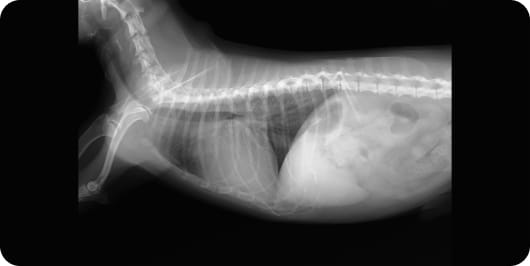

胸部レントゲン:心臓が拡大し、肺水腫(肺には水がたまっている)状態